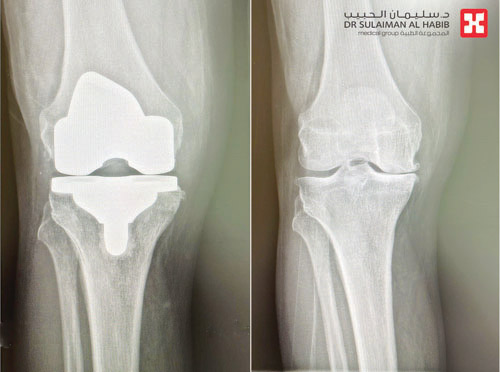

أجرى مستشفى الدكتور سليمان الحبيب بالقصيم، عملية نوعية وناجحة لاستبدال مفصل الركبة أنهت معاناة رجل يبلغ من العمر 56 عاماً مع خشونة واحتكاك وتلف غضاريف مفصل الركبة وأعراضها الشديدة التي نغّصت حياته وحدّت من حركته لفترة طويلة.

وقال د. عبدالله الشهراني استشاري جراحة العظام واستبدال المفاصل الصناعية، رئيس الفريق الطبي المعالج، إن المريض راجع المستشفى وهو يشكو من الآلام المتزايدة والتورم وتغير شكل مفصل الركبة اليمنى، بالإضافة إلى ضعف الحركة وصعوبتها، ورجح الفحص السريري المبدئي وجود احتكاك حاد في مفاصل الركب، وهذا ما أكدته الفحوصات التي خضع لها لاحقاً. وفي ضوء نتائج الفحوصات قرر الفريق أهمية إجراء عملية لاستبدال مفصل الركبة اليمنى بآخر صناعي. وتم إجراء عملية للمريض تم خلالها استبدال المفصل باستخدام مفصل صناعي خاص من نوع CR، وتكللت العملية التي استمرت 60 دقيقة بالنجاح ولله الحمد وتمكن المريض من المشي بعد نحو ساعتين وغادر المستشفى وهو بحالة صحية جيدة.

وأوضح د. الشهراني أن مفصل الركبة CR الذي استخدم في هذه الحالة، يتميز بأنه لا يتطلب قطع الرباط المتصالب الخلفي، ويقلل أيضاً من إزالة عظم الفخذ ويحافظ على سلامة الكثير من الأنسجة، مما يجنب المرضى الصعوبات المتمثلة في الآلام الحادة بعد العملية، وأيضاً طول مدتي التنويم والعلاج الطبيعي والتأهيل.